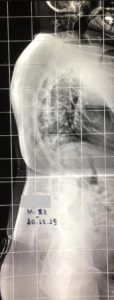

Εικόνα 6

Διεγχειρητική εικόνα τοποθέτησης των διαυχενικών κοχλιών με την καθοδήγηση από το σύστημα O-Arm. Παρατηρούνται οι συγγενείς σπονδυλικές ανωμαλίες.

Οπτικά δια των γενόμενων χειρισμών επί της Σπονδυλικής Στήλης, διαπιστώθηκε ότι υπήρχε πλήρης κατάργηση της κινητικότητάς της σε όλα τα επίπεδα, λόγω των οστικών γεφυρών που είχαν δημιουργηθεί μεταξύ των ημισπονδύλων.

Μετά την τυπική παρασκευή των μαλακών μορίων και απομάκρυνση αυτών σε όλη την έκταση του Θωρακο-οσφυϊκού κυρτώματος, πραγματοποιήθηκε από τη δεξιά μεριά οστεοτομία τύπου Eggshell στο σώμα του κορυφαίου σπονδύλου-ημισπονδύλου του κυρτώματος και ολοκληρωτική αφαίρεση δια πολλαπλών τοπικών οστεοτομιών των αρθρώσεων (Facets), μίσχων (Pedicles) των υπερκείμενων και υποκείμενων ημισπονδύλων, καθώς και τμημάτων των πλευρών και των πλευρο-σπονδυλικών αρθρώσεων.

Προ της πραγματοποίησης των οστεοτομιών τοποθετήθηκαν οι διαυχενικοί κοχλίες. Η τοποθέτησή των ήταν εξαιρετικά δυσχερής, λόγω των μικρών διαστάσεων των μίσχων (pedicles) και των σπονδυλικών σωμάτων γι’ αυτό το μήκος και η διάμετρος των κοχλιών ήταν πολύ μικρή για να μπορέσουν να προσαρμοσθούν στις υφιστάμενες σπονδυλικές διαστάσεις.

Σε μερικούς σπονδύλους ήταν τελείως αδύνατη η τοποθέτηση κοχλιών λόγω μικρών διαστάσεων των μίσχων (pedicles). Ακολούθως με μεγίστη προσπάθεια περιορίσθηκε το άνοιγμα της οστεοτομίας του σπονδυλικού σώματος, λόγω της μηδενικής ελαστικότητας του πλευρο-σπονδυλικού συστήματος. Η χειρουργική επέμβαση ολοκληρώθηκε με τη τοποθέτηση ομολόγων οστικών μοσχευμάτων.

6. Στους υπόλοιπους, εκεί που κατορθώθηκε με τη καθοδήγηση του O-ARM να τοποθετηθούν κοχλίες, αυτοί είχαν πολύ μικρές διαμέτρους (3,5-4,5 χιλιοστά) και μικρά μήκη επίσης περί τα 35 χιλιοστά, λόγω των μικρών διαστάσεων των σπονδυλικών σωμάτων και των τόξων .

Εικόνα 19 : Διεγχειρητικές φωτογραφίες που έχουν ληφθεί από την οθόνη προβολής των εικόνων κατά την τοποθέτηση των κοχλιών με τη καθοδήγηση από το σύστημα πλοήγησης O-ARM.

Παρατηρούνται οι πολύ μικρές διαστάσεις των σπονδυλικών σωμάτων των μίσχων (pedicles) και των διαυχενικών κοχλιών.